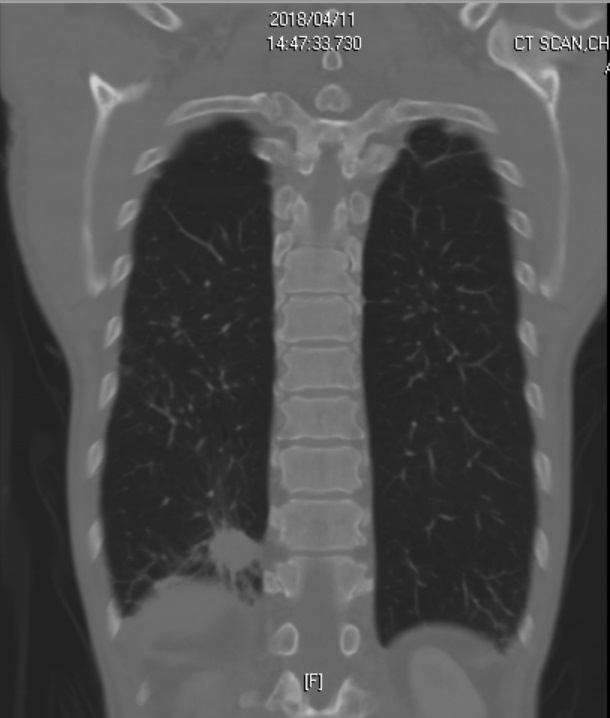

Figure 2. Chest CT image

Diffuse emphysema of both lungs with focal bronchiectasis and bronchial wall thickening is mentioned with peribronchial infiltrates and small peribronchial nodules(more obvious in RUL and LUL). The possibility of COPD with chronic bronchiolitis is more likely than lung to lung metastasis.

A solid mass 3cm is located in basal segment of RLL of lung with pleural retraction. Lung cancer can not be ruled out.